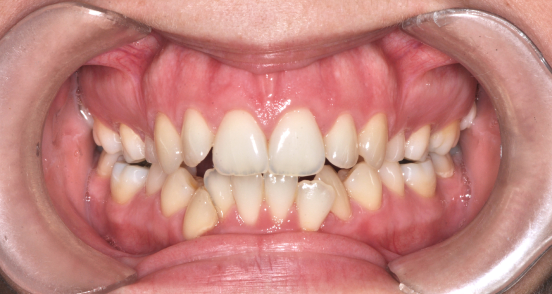

Előtte fogsor - Nyitott harapás kezelése állcsontműtéttel

A kiindulási állapotban elöl nem jött létre fogérintkezés.

A nyitott harapás hátterében állcsonti pozíciós eltérés állt, nem a fogak helyzete.

Fogszabályozással előkészítettük a műtétet, majd állcsonti korrekciót végeztünk.

A felső állcsont helyzetének módosításával zártuk az elülső harapást,

az alsó állkapcsot pedig funkcionálisan stabil pozícióba állítottuk.

Eredmény: zárt, terhelhető harapás, javuló rágófunkció, stabil ízületi helyzet.